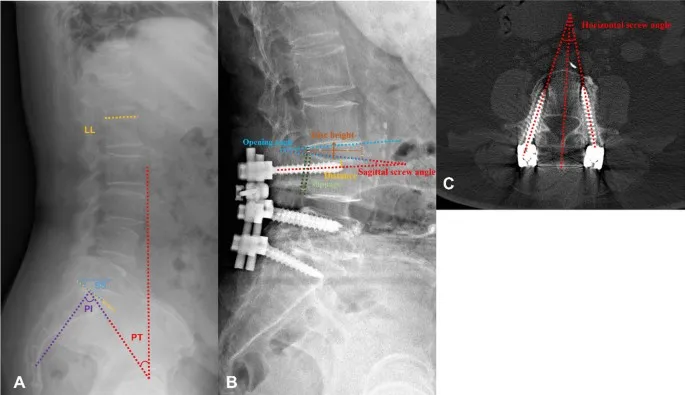

- X-ray (AP/Lateral/Flexion-Extension): Initial check for alignment, hardware integrity, and instability.

- CT Scan: 🥇 Gold standard for evaluating bony fusion (arthrodesis). Best modality to visualize pseudarthrosis (failed fusion).

- MRI: Assesses soft tissues. Indicated for new/worsening neurologic deficits to rule out hematoma, abscess, or persistent nerve compression.

⭐ Pseudarthrosis: A key complication seen as a radiolucent gap at the fusion site on CT, often with motion on dynamic X-rays. It's a major cause of "failed back surgery syndrome."